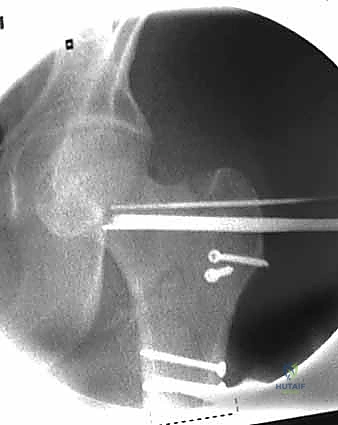

2. الرد المغلق تحت جهاز الأشعة (Closed Reduction)

قبل إجراء أي شق جراحي، يقوم الدكتور هطيف بسحب الساق وتدويرها بمهارة فائقة لإعادة العظام المكسورة إلى مكانها الطبيعي (المحاذاة التشريحية). يتم التأكد من ذلك باستخدام جهاز الأشعة السينية المتحرك داخل غرفة العمليات (C-Arm Fluoroscopy). هذه الخطوة حاسمة، فالرد الجيد يعني التئاماً ممتازاً.

4. إدخال السلك الدليلي (Guide Wire)

يتم إدخال سلك معدني رفيع جداً عبر العظم باتجاه رأس الفخذ تحت توجيه الأشعة المستمر. هذا السلك يعمل كمسار دقيق سيتبعه المسمار النهائي. يجب أن يكون السلك في الموضع الهندسي المثالي لتجنب اختراق مفصل الورك.

5. الحفر وتثبيت الغرسة (Reaming and Implantation)

يتم استخدام أداة حفر مجوفة تمر فوق السلك الدليلي لتوسيع مسار في العظم. بعد ذلك، يتم إدخال المسمار الرئيسي القوي (سواء المسمار المنزلق أو المسمار النخاعي).

6. التثبيت النهائي (Locking)

لضمان عدم تحرك الغرسة، يتم تثبيتها بمسامير إضافية أصغر في جسم عظم الفخذ. هذه المنظومة الميكانيكية توفر ثباتاً استثنائياً يسمح للمريض بتحريك ساقه فور استيقاظه من التخدير.

مجموعة من الصور الإضافية التي توضح مراحل دقيقة من العمل الجراحي المعقد الذي يجريه الأستاذ الدكتور محمد هطيف لضمان أعلى درجات الدقة الميكانيكية الحيوية: